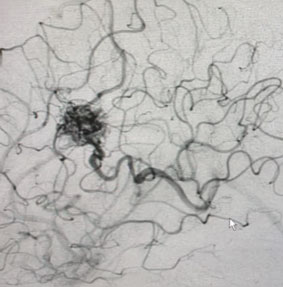

Head CT was consistent with a small acute left intraventricular hemorrhage (Figure 1).

Fig. 1